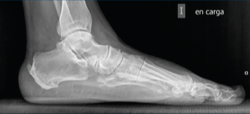

Figura 4. Imagen fluoroscópica de la fresa suelta introducida y su correspondencia en cirugía.

Ayudándose del mosquito para separar las partes blandas, se introduce una fresa Shannon 2 o 3 × 20 mm (FH Orthopedics, Mulhouse, Francia) en el vértice de la V. Comprobada la correcta posición de la fresa en la fluoroscopia (desconectando el motor de la fresa) (Figura 4), esta se avanza perpendicularmente al eje del calcáneo hasta atravesar la segunda cortical. Inclinando la fresa se pueden obtener diferentes desplazamientos, si bien, para conseguir un mayor desplazamiento, se recomienda avanzar perpendicularmente al eje. Si se quiere conseguir cierto efecto de descenso además de medialización de la tuberosidad se dirigiría la fresa en dirección de dorsolateral a plantomedial unos 15-30° respecto a la perpendicular del eje del calcáneo. Si lo que se quiere es obtener un efecto de elevación (beneficioso en el cavo posterior), la dirección sería la contraria, es decir, de lateroplantar a dorsomedial. Se podría obtener también acortamiento del calcáneo si la fresa se dirige de lateral distal a medial proximal, e incluso un alargamiento (de lateral proximal a medial distal), aunque esto último dificultaría el desplazamiento por la tensión de los tejidos(13).

Figura 5. Imagen fluoroscópica del trazo dorsal de la osteotomía y su correspondencia en cirugía.

La fresa se coloca en línea con el trazo de osteotomía dibujado en la piel, primero el dorsal y después el plantar (Figuras 5 y 6), y va cortando la pared lateral y el hueso esponjoso del calcáneo y progresando paulatinamente hasta alcanzar la segunda cortical y cortarla cuidadosamente. Se recomienda no superar en 6.000 rpm la velocidad de la fresa para evitar la osteonecrosis térmica. A pesar de que el procedimiento se realiza sin isquemia para que la sangre refrigere el calor de la fresa, se recomienda que el ayudante aporte suero salino para contribuir a tal efecto.

Figura 6. Imagen fluoroscópica del trazo plantar de la osteotomía y su correspondencia en cirugía.